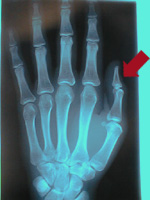

Description: broke left thumb and sprained right wrist on one fall on a dry slope.

Fracture: outer left thumb;

Treatment: Bandages, splints used for 3 months;